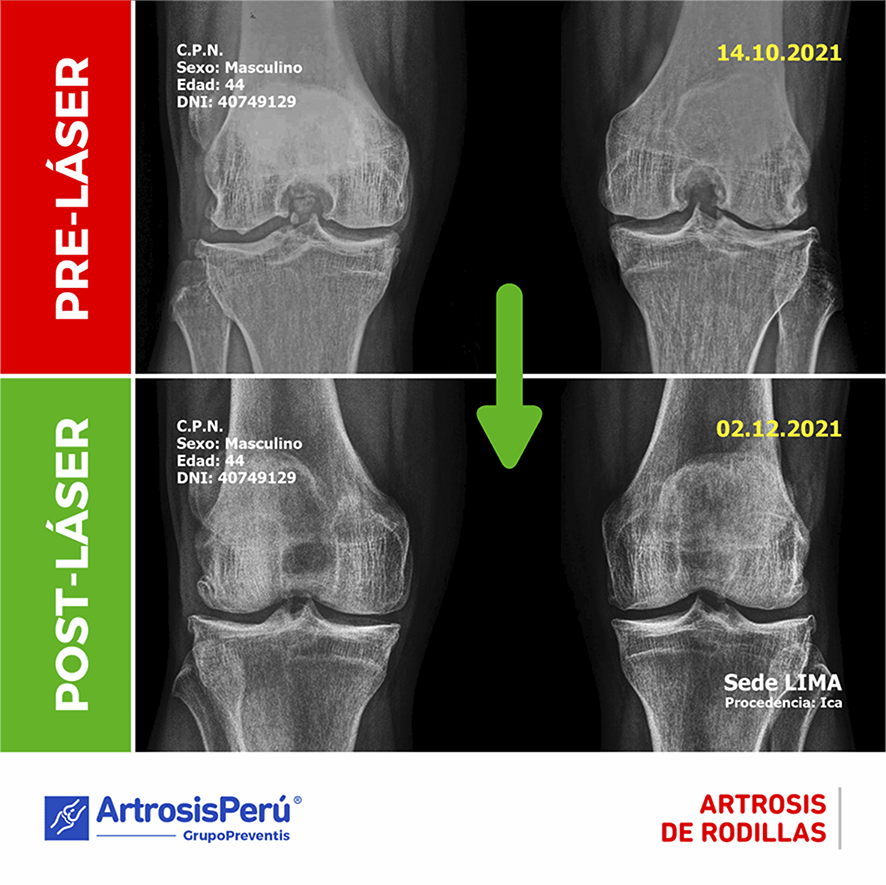

TECNOLOGÍA ROBÓTICA LÁSER

Empleamos Tecnología Robótica Láser aprobada por FDA (www.fda.gov) y autorizada en nuestro país por el Ministerio de Salud (DIGEMID). Esta tecnología le permite a nuestro especialista localizar y revitalizar tejidos enfermos y/o lesionados que aún puedan recuperarse, gracias a que logra:

- Restaurar el cartílago articular y el disco vertebral aún viable.

- Restaurar el colágeno estructural de huesos y vértebras.

- Producir un efecto analgésico antiinflamatorio potente y rápido.

Esta moderna técnica es actualmente el último recurso antes de considerar una cirugía convencional. Se realiza desde la superficie de la piel, sin cortes, sin anestesia, sin riesgos y es altamente efectiva.